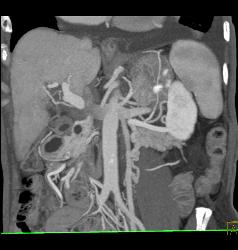

Gastric Cancer With Tube in Antrum Due to Obstruction- See Full Sequence